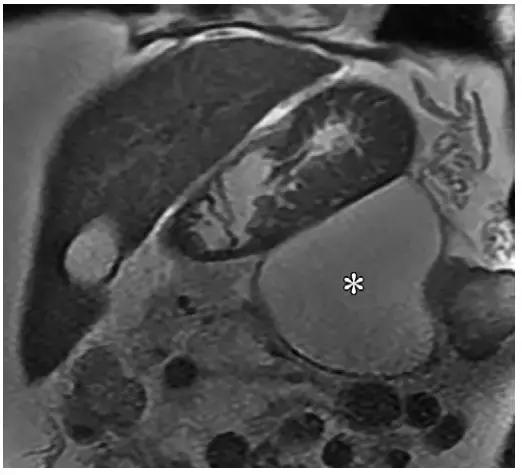

在 MR 成像中,假性囊肿表现为均匀高 T2 信号(图 6)。MRCP 具有高组织分辨率,可以显示部分假性囊肿与胰管相通(图 7)。

4 周以后,ANC 逐渐形成成熟的壁,进展为 WON。同假性囊肿相似,WON 包括液性物质和可明显强化的厚壁。但与假性囊肿不同的是,WON 含有坏死脂肪或胰腺组织,在增强 CT 和 MR 图像中表现为液体内含有非液性成分(图 3c,10)。

WON 可存在于胰腺实质,但更常见于胰周,也可同时累及胰腺和胰周(图 10)。有研究表明,对于病程超过 4 周胰腺炎,MR 的评估能力高于 CT。

MR 成像可以显示坏死物的数量,因此在制作手术计划时,MR 成像可作为增强 CT 的替代方法(图 11)。